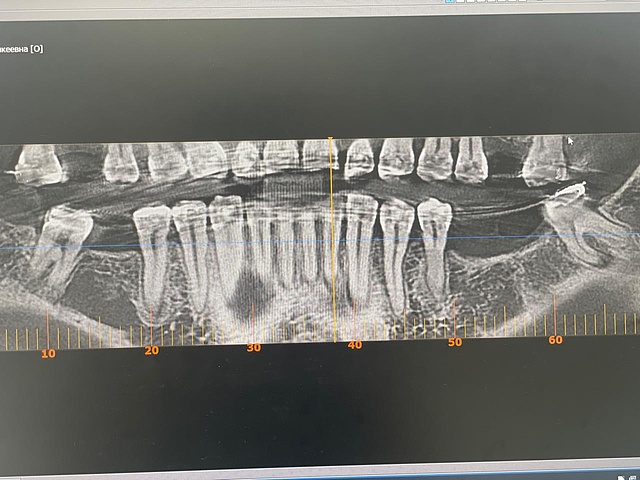

Понравилась знакомая и родная упаковка имплантата. Сам имплантат вариативен по размерам и имеет выраженную резьбу. На верхней челюсти стабилизация имплантата не составила труда, даже небольшой переизбыток торка. Хирургический набор тоже напомнил стандартный набор импро, интуитивно понятное использование сверел. Заглушка в комплекте тоже некий плюс в копилку импро.Пациент: Г., женщина, 43 года, пациент на ортодонтическом лечении

Ранее зубы 46,36,37 удалены по поводу осложненного кариеса. На КЛКТ снимке костное предложение позволяет установить имплантаты 5,5х9,5 в позиции 36 и 37 Зубов. Справа установлен Эниридж 4,5х10.На нижней челюсти установка имплантата прошла по другому протоколу, так как плотность кости выше, чем на верхней. Хирургический набор позволил с легкостью установить имплантаты, с хорошим торком. Далее по плану принято решение о пластике мягких тканей вокруг имплантатов с установкой ФДМ. И протезирование временное, затем постоянное.